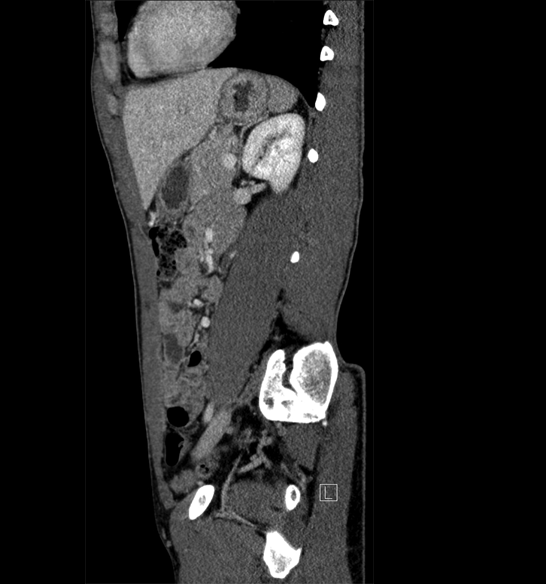

Body

Covers abdominal CT anatomy.